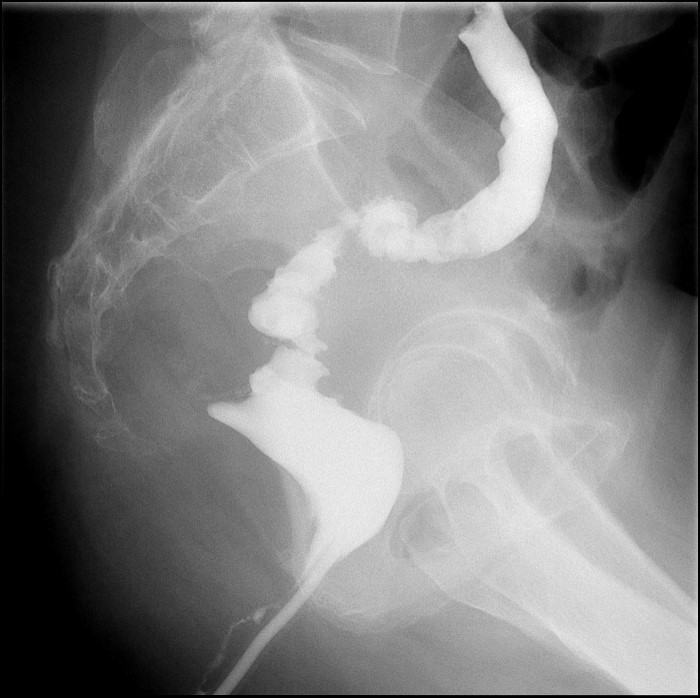

- The gynecologist will begin injecting contrast material into the uterus. Obtain images periodically throughout the procedure (usually at the direction of the gynecologist). The images should include the uterine cavity filled with contrast material, bilateral fallopian tubes filled with contrast material, and spillage and dispersion of contrast material into the peritoneal cavity (image 1) (image 2) (image 3) (image 4) (image 5).